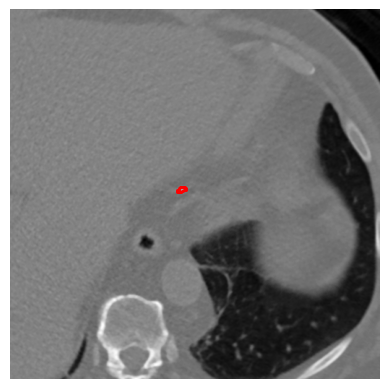

Coronary artery disease (CAD), one of the leading causes of mortality worldwide, necessitates effective risk assessment strategies, with coronary artery calcium (CAC) scoring via computed tomography (CT) being a key method for prevention. Traditional methods, primarily based on UNET architectures implemented on pre-built models, face challenges like the scarcity of annotated CT scans containing CAC and imbalanced datasets, leading to reduced performance in segmentation and scoring tasks. In this study, we address these limitations by incorporating the self-supervised learning (SSL) technique of DINO (self-distillation with no labels), which trains without requiring CAC-specific annotations, enhancing its robustness in generating distinct features. The DINO-LG model, which leverages label guidance to focus on calcified areas, achieves significant improvements, with a sensitivity of 89% and specificity of 90% for detecting CAC-containing CT slices, compared to the standard DINO model's sensitivity of 79% and specificity of 77%. Additionally, false-negative and false-positive rates are reduced by 49% and 59%, respectively, instilling greater confidence in clinicians when ruling out calcification in low-risk patients and minimizing unnecessary imaging reviews by radiologists. Further, CAC scoring and segmentation tasks are conducted using a basic UNET architecture, applied specifically to CT slices identified by the DINO-LG model as containing calcified areas. This targeted approach enhances CAC scoring accuracy by feeding the UNET model with relevant slices, significantly improving diagnostic precision, reducing both false positives and false negatives, and ultimately lowering overall healthcare costs by minimizing unnecessary tests and treatments, presenting a valuable advancement in CAD risk assessment.